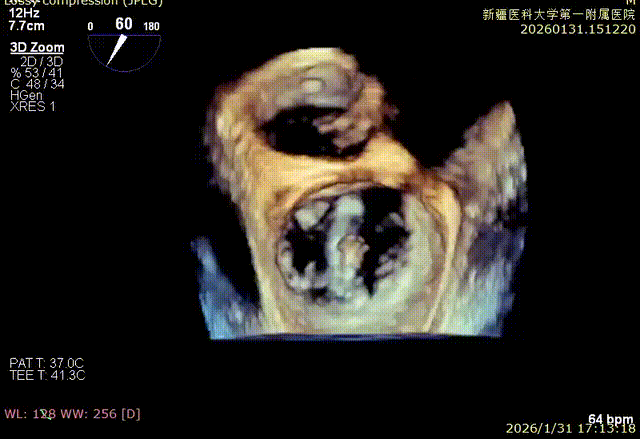

3D enface 切面

3D enface观察反流

3D enface 观察后叶栓系